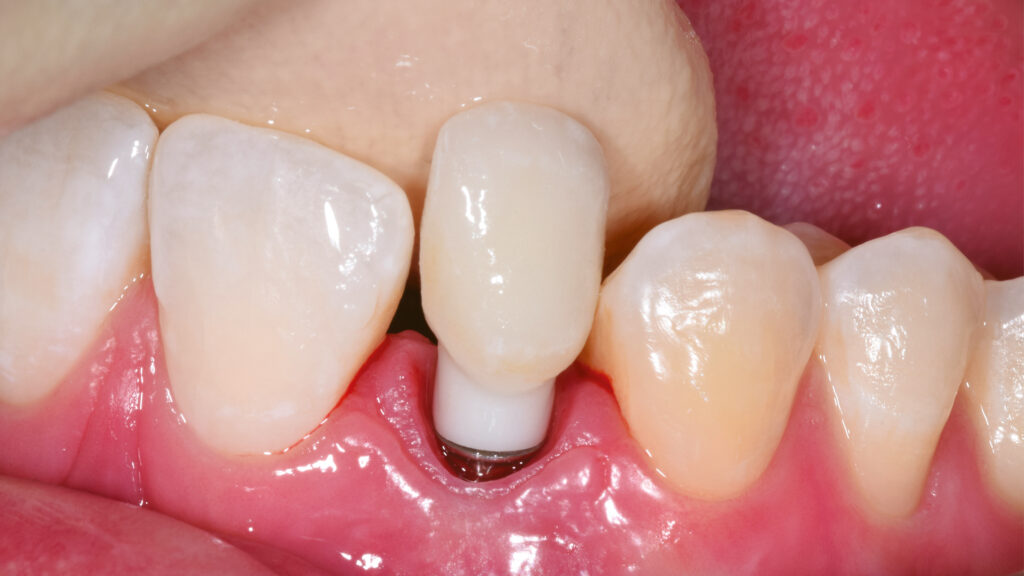

Die Gestaltung des marginalen Randes („Präparationsrand”) im bukkalen Bereich erfolgt in Absprache mit dem Zahnarzt ca. 0,2 mm subgingival (Abb. 52). Palatinal endet die Verblendkeramik supragingival, um hier die biologischen Vorteile des Zirkonoxids zu nutzen (Weichgewebekonditionierung) (Abb. 53). Vor allem im Frontzahnbereich wird das individualisierte Emergenzprofil als wichtiger Faktor für die Rekonstruktion einer zufriedenstellenden Ästhetik angesehen. Zudem werden im Frontzahnbereich mit Zirkonoxid biologisch und ästhetisch bessere Ergebnisse erzielt als mit Titan, das bei dünnem Gingiva-Biotyp durchscheinen kann (Abb. 54 und 55).

Die individuelle Formgebung der ASC-Implantatkronen ermöglicht einen reizfreien Schleimhautkontakt mit Titanadapter und konischer Innenverbindung zum Implantat (Abb. 56 und 57). Die keramische Verblendung des Zirkonoxid-Abutments erfolgt analog und ebenso detailgetreu wie beim keramischen Veneer und mit der gleichen Verblendkeramik (Lumex AC). Nach der Verblendung wird die Implantatkrone auf dem Meistermodell verschraubt und eine letzte Kontrolle der Kontaktflächen (Abb. 58 und 59), der Artikulation, der seitlichen Bewegungen und der Eckzahnführung durchgeführt. Abbildung 60 zeigt den nahtlosen Übergang der Implantatkrone zur natürlichen Gingiva. Eine Überkonturierung könnte zu einer apikalen Verschiebung führen. Eine polar_eyes-Aufnahme macht das Innere der Krone und die Details besser sichtbar (Abb. 61).

Ergebnis ist eine ästhetisch hochwertig verblendete Implantatkrone auf einem individuellen Zirkonoxidgerüst mit Titanadapter. Die mesiale Ansicht zeigt das Emergenzprofil und eine vertikale Achsneigung, die quasi von inzisal zur Implantatmitte verläuft. Der subgingivale Anteil tritt schlank aus dem Implantat aus und unterstützt mit einem konvexen Übergang zur Implantatkrone das Niveau der Gingiva (Abb. 62). Die Abutmentbasis aus Titan sorgt für eine präzise Passung, die gut kontrollierbar ist. Abbildung 63 zeigt die verschiedenen Komponenten der Implantatrestauration: Titanadapter, eine Omnigrip-Schraube und Omnigrip-Schraubendreher sowie die Vollkeramikkrone.